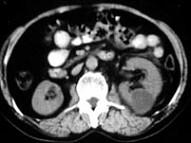

问题 女,55岁,发热,左侧腰部痛胀不适4天,CT检查如图所示,下列说法错误的是 ( )

选项 A、考虑为多囊肾合并感染 B、考虑为多发肾囊肿合并感染 C、病灶境界清晰,囊内密度近似水的密度 D、肾前筋膜增厚 E、左肾上极和下极各可见一个类圆形的囊性病灶

答案 A